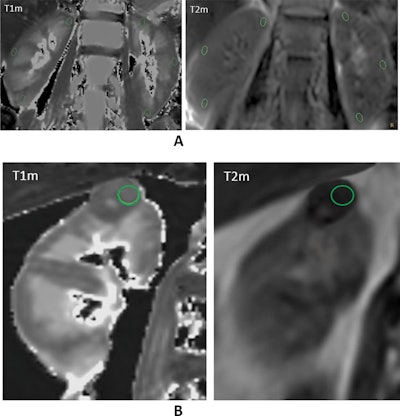

Examples of native T1 and T2 mapping in the reference group and renal mass cohorts with region of interest (ROI) delineation. A: Native T1 mapping (left) and T2 mapping (right) coronal raw images of normal kidneys. Three oval ROIs measuring 0.30cm2 were manually drawn at the same symmetrical location of the left and right kidneys, including the superior, middle, and inferior pole of the cortex. B: Native T1 mapping (left) and T2 mapping (right) coronal image of an oncocytoma of the upper pole of the right kidney (maximum diameter: 3 cm). A freehand circular ROI in the tissue part of the mass was set at 1.0cm2.Images courtesy of Dr. Remy Henry, Prof. Catherine Roy, et al, and European Journal of Radiology.

The group recorded the renal cortex values of 125 patients with normal kidneys (reference group) and 75 patients with renal masses on a clinical 3-tesla MRI unit (Ingenia CX, Philips) and a standard 32-channel torso phased-array coil using T1m and T2m sequences. For the quantitative evaluation, measurements were performed by delineating regions of interest (ROIs) on T1m and T2m sequences in the renal cortex of the reference group and in renal masses.